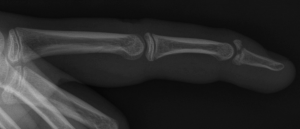

X-ray of mallet finger

- Request a finger X-ray of the affected digit. This should have PA (posterior-anterior), oblique, and lateral views.

- Look for a dorsal avulsion fracture of the distal phalanx at DIP joint.